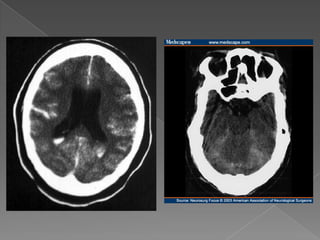

 Primer estudioen el abordaje  Cortes de 3 mm. desde la base del cráneo.  Paralela al paladar duro.  Hemoglobina < 10 gr/dl aparece isodensa.  Artificios por movilización del paciente. Am J Emer Med 2006;24:859-863

 Predecir lalocalización 70%  Hemorragia intraventricular (PICA)  Hemorragia en la cisura interhemisférica (Acom)  Hemorragia en el valle silviano (ACM / com post)